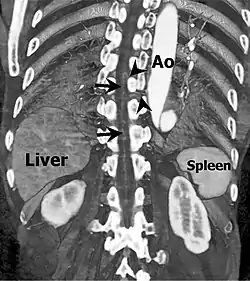

Coronal slab volume rendering image of CT aortography shows artery of Adamkiewicz entering spinal canal(arrowheads) and joining the anterior spinal artery (arrows) after a hairpin turn. | |